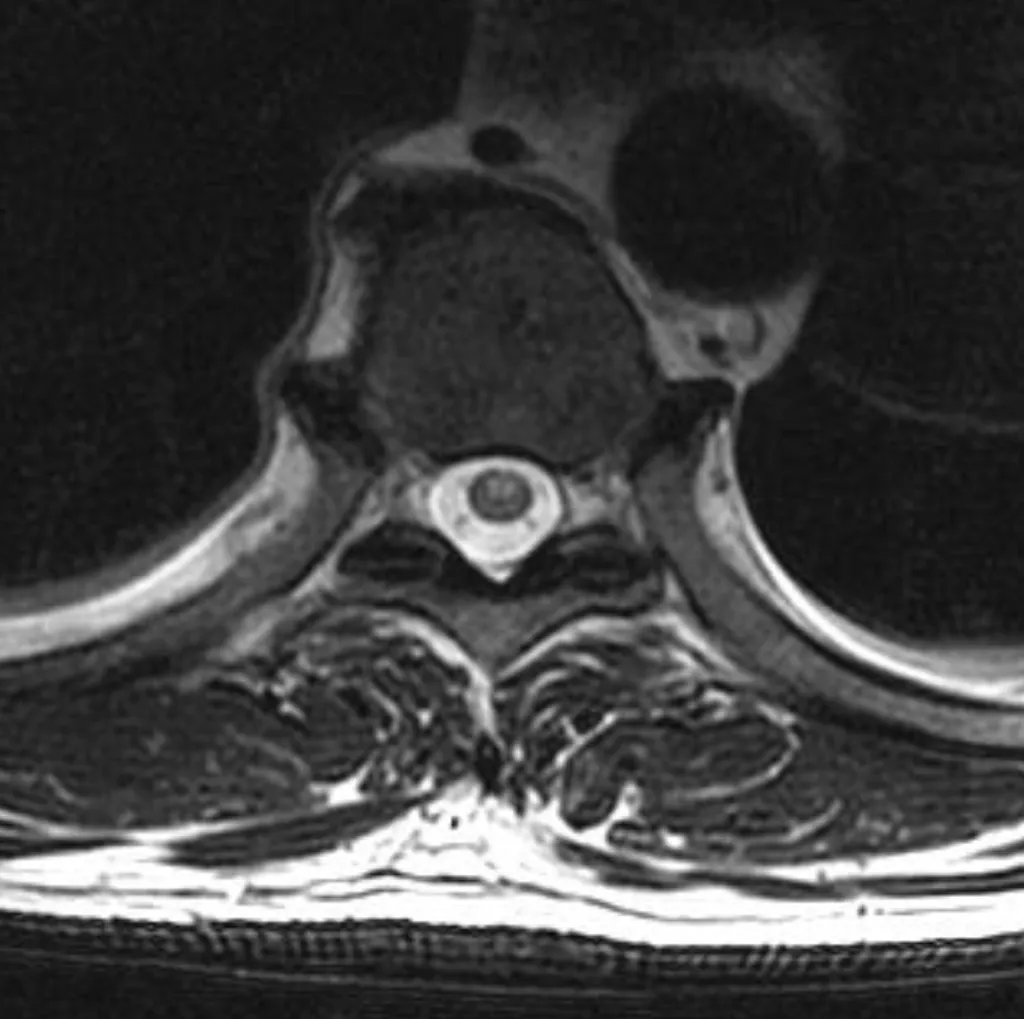

【114-1 醫學(六) 第72題】

51 歲男性主訴跌倒後數小時開始出現四肢無力且大小便失禁,圖為病人的胸椎磁振造影影像(T2WI),下列敘述何者錯誤?